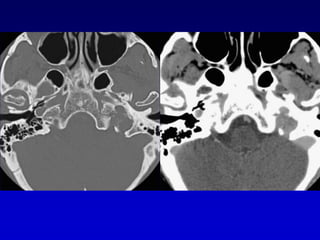

Carótida aberrante

Bulbo yugular dehiscente